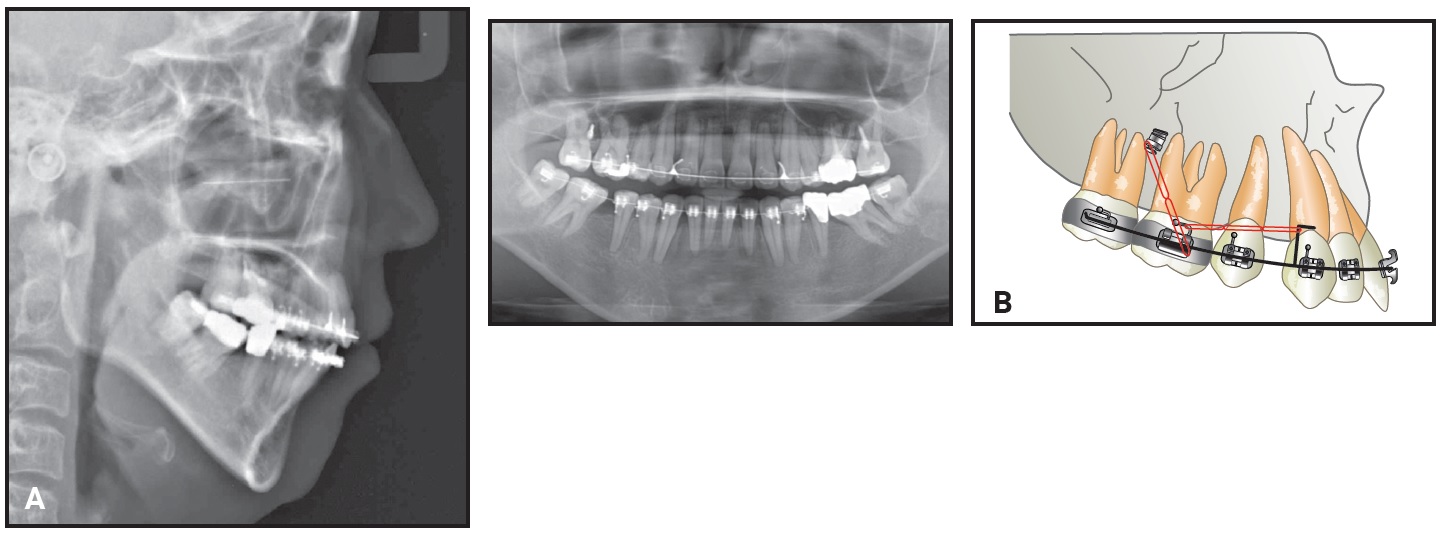

Standard-prescription .022" Damon MX* self-ligating brackets were bonded in both arches, except for the lingually displaced lower right central incisor. One month later, an open-coil spring was inserted mesial to the lower right canine on the initial .014" Copper NiTi archwire to open space for the displaced incisor (Fig. 2).

Fig. 2 Initial .014" Copper NiTi** archwire with U-shaped segmental wire in lower anterior segment.

A segmental U-shaped arch was added and slightly activated distally to control the lower incisors while avoiding any protrusion. The .014" Copper NiTi archwire was maintained for seven months, until the wire was completely passive in the slots, and was then replaced by an .014" × .025" Copper NiTi archwire. Minor interproximal stripping of the lower incisors was performed to facilitate leveling and alignment.

The lingually displaced lower right incisor was bonded after 23 months of treatment, when sufficient space had been opened for its traction and alignment. Torque control was then needed to align the roots of the lateral incisor buccally and the central incisor lingually. Because it is difficult to control torque on a round archwire, an inverted, U-shaped .017" × .017" TMA* segmental wire was inserted into the vertical bracket slots (Fig. 3). The .014" × .025" Copper NiTi archwire was inserted passively to control torque in all teeth until uprighting and alignment were complete.

Fig. 3 After 23 months of treatment, showing torque control of lower right central and lateral incisors with inverted, U-shaped .017" × .017" TMA** wire in vertical slots.

In the Damon System, the patient’s archform is recorded with a wax bite registration at this stage, allowing for complete expression of the perioral musculature and the alveolar bone remodeling that occurs after arch expansion.9 The system then provides further expansion in the canine, premolar, and molar regions. In this case, the diagrammed .017" × .025" TMA archwires were inserted after 28 months of treatment for additional torque control and arch preparation. Finishing .019" × .025" TMA archwires were used for the last month (Fig. 4).

Fig. 4 After 34 months of treatment, showing .019" × .025" TMA finishing archwires.